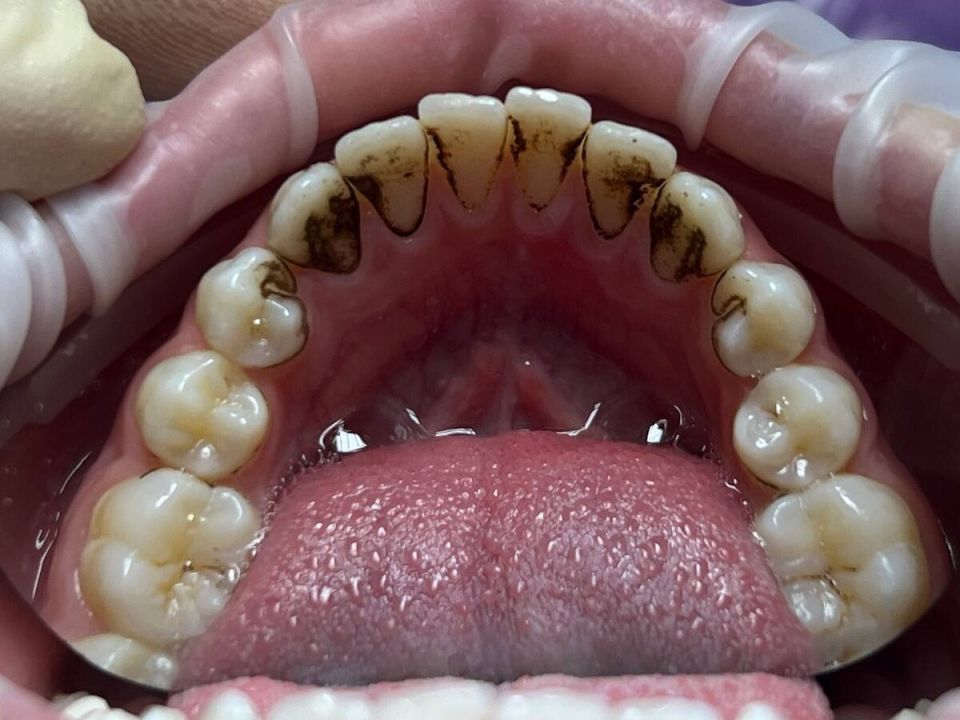

Налет Присли — это специфический вид зубного налета, часто встречающийся у детей. Его главные характеристики:

- Плотная текстура и темный цвет — оттенки варьируются от коричневого до почти черного.

- Чаще всего образуется в области дёсен и на внешней поверхности зубов.

- Не поддается удалению с помощью обычной зубной щетки или пасты.

- Создает эстетический дискомфорт, даже если зубы по здравоохранению остаются здоровыми.